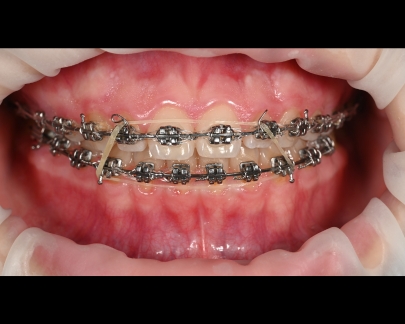

Sunt benzi elastice mici, din latex, folosite pentru corectarea mușcăturii și intercuspidarea dinților.

Elasticele se atașează de brackeții dinților superiori, respectiv inferiori și vin în diferite dimensiuni și grade de forță.

![]() | ![]() |

Elasticele ortodontice corectează raportul dintre maxilar și mandibulă (mușcătura). Sunt purtate conform indicațiilor medicului și sunt esențiale în multe tratamente pentru alinierea corectă a arcadelor.